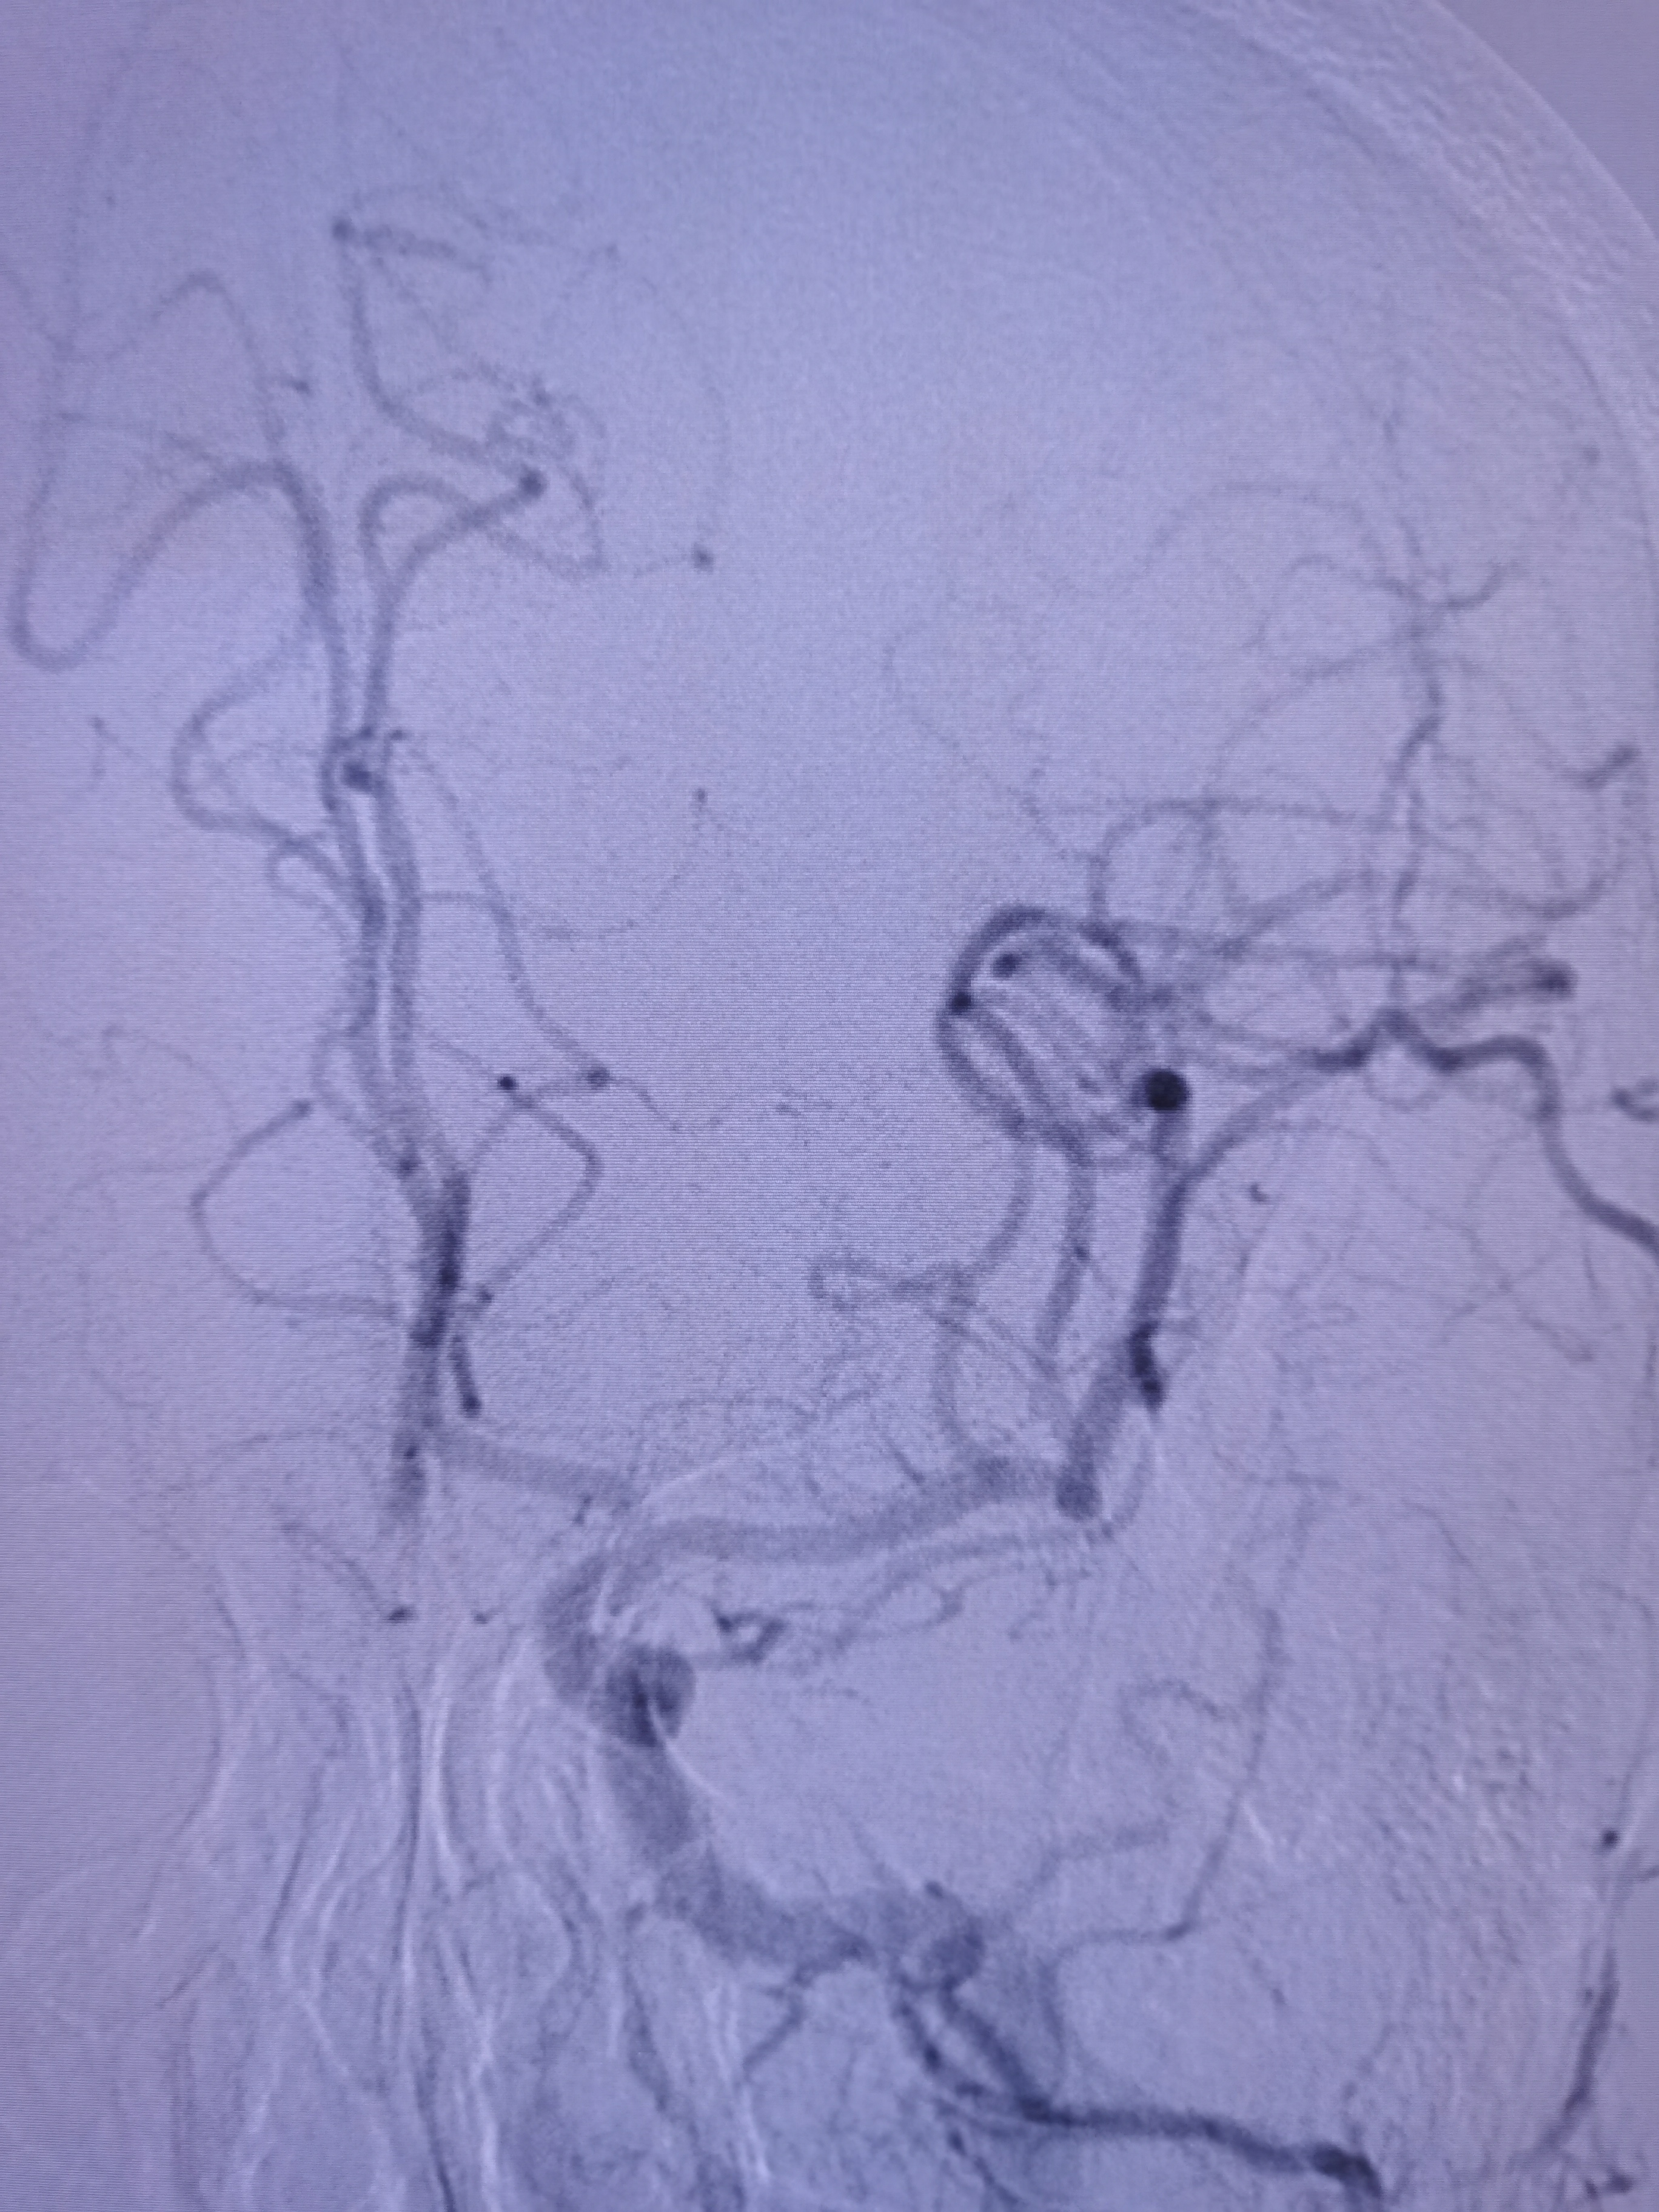

左侧颈内动脉狭窄伴溃疡形成。

颅内段显影可。

双侧大脑前动脉共干。

将导引导管调至左侧颈总动脉末端,远端置入保护伞。

9/30支架定位。

支架释放后狭窄改善,覆盖不稳定斑块。

支架释放后颅内血供良好。

颅内血供良好。